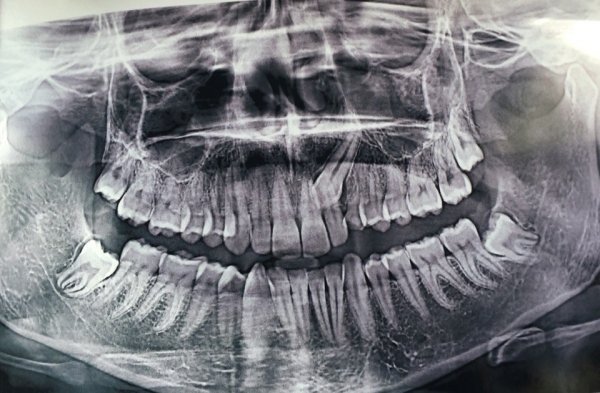

Для установления брекетов врач мне рекомендует удалить верхнюю справа четверку, чтобы поставить на ее место клык, и нижний второй резец справа, аргументируя тем, что так будет быстрее идти лечение, по словам врача корень у этого резца оголен и подвижен (хотя я не чувствую, чтобы он шевелился) и, что все равно в дальнейшем этот зуб я потеряю (и никто, кроме стоматологов не будет замечать, что резцов нижних у меня 3, вместо 4х).

Правда ли то, что этот зуб (резец второй) не здоров? И лучше удалить его, а не 4 нижнюю справа?

По снимку невозможно диагностировать подвижность зуба. Существует методика, при которой возможно удаление и всех восьмых зубов, и, если потребуется, четверок.